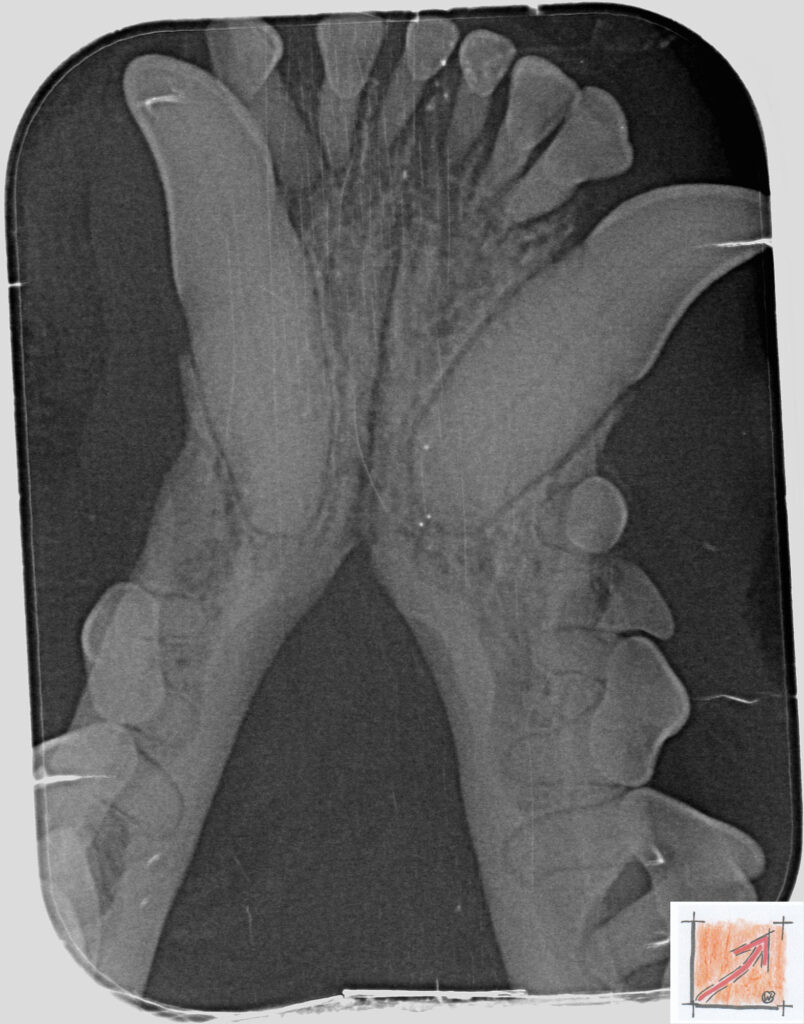

Röntgenbilder vom Thierrischen Orakel bei der Zahn-OP:

Warum Dentalröntgen beim Chihuahua lebenswichtig ist:

Ein Blick hinter die Kulissen von Chihuahua-Zähnen:

In dieser Galerie zeigen wir exklusive intraorale Röntgenaufnahmen einer Zahn-Operation beim Thierrischen Orakel als Chihuahua vom BauFachForum. Während oberflächlicher Zahnstein oft sichtbar ist, verbirgt sich die wahre Gefahr für das Herz meist unter dem Zahnfleischsaum.

Das digitale Dentalröntgen ist der Goldstandard in der modernen Tiermedizin, um parodontale Entzündungsherde und Wurzelabszesse sicher zu diagnostizieren. Für Chihuahuas wie dem Thierrischen Orakel, mit Mitralklappeninsuffizienz ist dieser diagnostische Schritt essenziell. Nur wenn versteckte Bakterienherde an der Zahnwurzel oder mit dem Fachbegriff Apikalabszesse erkannt und saniert werden, kann das Risiko einer bakteriellen Endokarditis oder einfach ausgedrückt einer Herzinnenhautentzündung minimiert werden.

Unsere Aufnahmen von Patienten dem Thierrischen Orakel verdeutlichen den Unterschied zwischen einer rein optischen Zahnreinigung und einer medizinisch fundierten Sanierung unter Röntgenkontrolle.

Chihuahua Mitralklappeninsuffizienz Trachealkollaps:

Wichtig ist im Vorfeld die Zahnhygiene des Chihuahuas. Die Bilder zeigen Dentale Röntgenbilder vom Thierrischen Orakel als Chihuahua-Hund während seiner Zahn-OP. Darstellung von Kieferknochen und Zahnwurzeln zur Diagnose von Parodontitis.

Zahnröntgenaufnahme bei Chihuahua Thierry:

Untersuchung der Zahnwurzeln auf Entzündungsherde als Prophylaxe gegen bakterielle Endokarditis.

Intraorales Dentalröntgen eines Chihuahuas:

Die Bilder zeigen Zähne und Wurzelstrukturen im Unterkiefer zur Planung einer Extraktion bei hochgradigem Zahnstein.